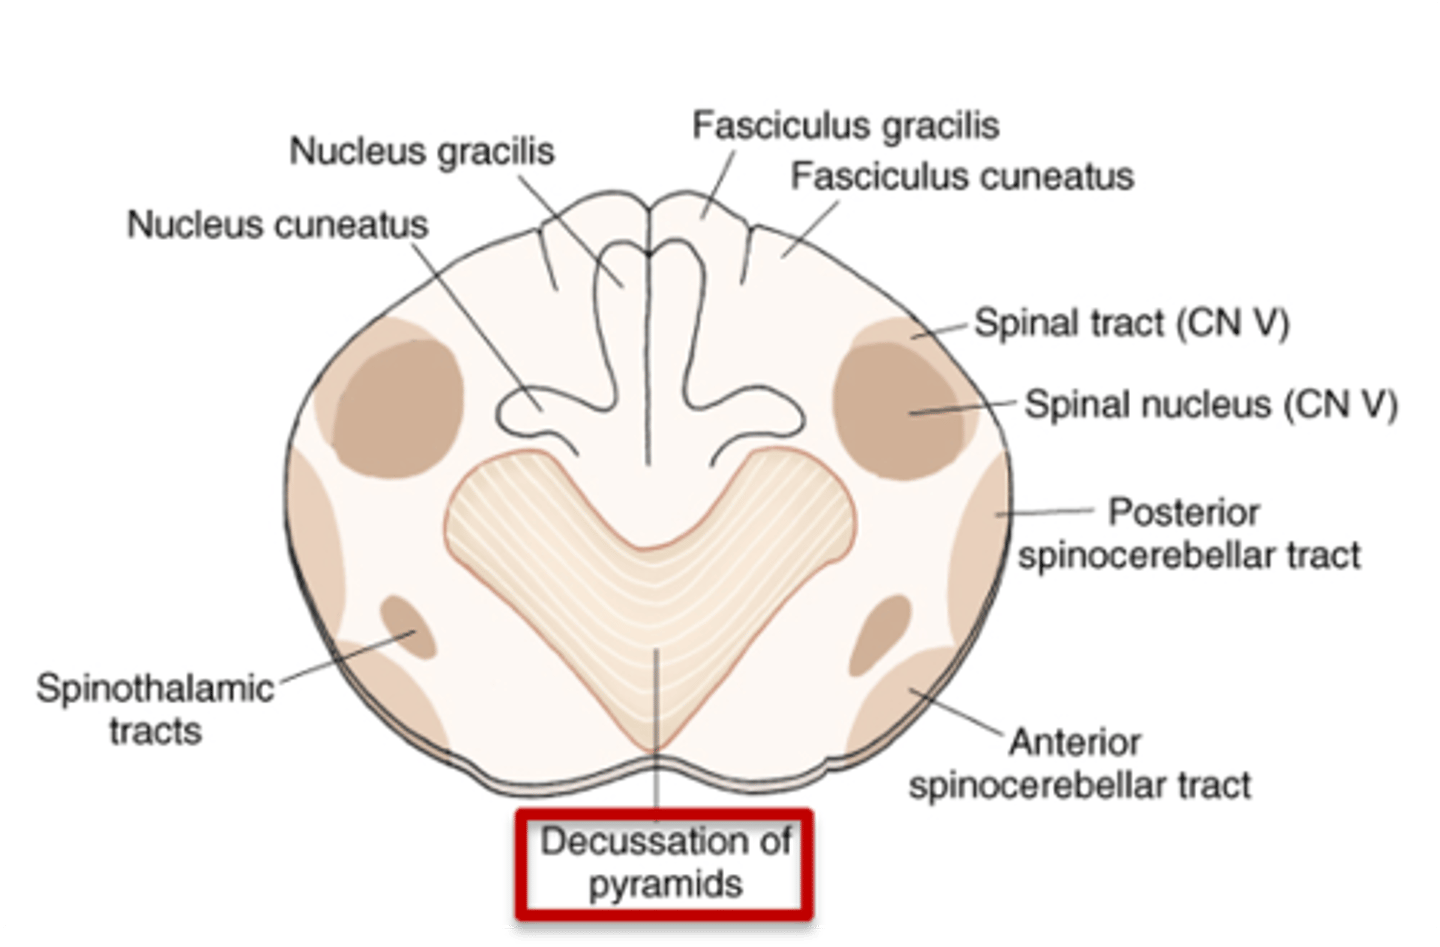

what region of the brainstem contains a motor (pyramidal) and sensory decussation?

medulla

which decussation of the medulla is the site of crossing of the dorsal column-medial lemniscus fibers (DC/ML) in the caudal medulla?

sensory decussation